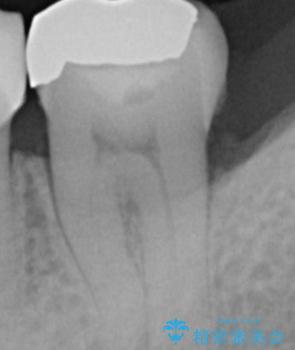

- 銀の詰め物を白くしたいとの事で来院。

銀の詰め物を外し、拡大鏡下でう蝕を全て取り除いたのを確認して

e-maxインレーにて治療しました。